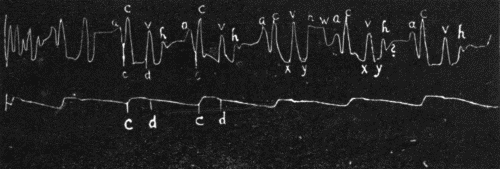

35. Events in the cardiac cycle124

36. Simultaneous tracings of the jugular and carotid pulses125

37. Jugular and carotid tracings125